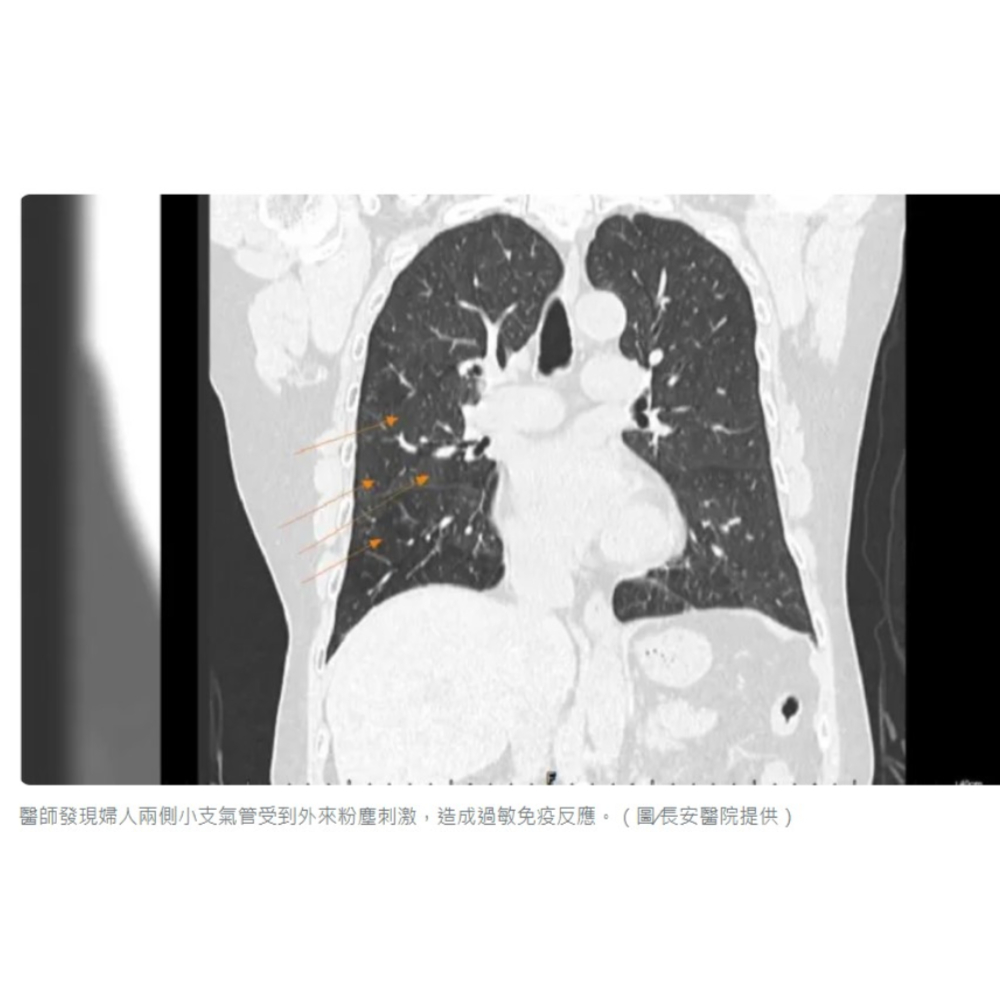

寧姓婦人因長期氣喘合併慢性咳嗽、胸悶多年,醫師檢查發現患者胸部X光只看到些微浸潤與腫脹,但經過電腦斷層檢查,能清楚看到兩側肺野(肺在胸片上表現為均勻一致且較透明的區域)有典型的拼布狀塊狀變化,長安醫院胸腔內科醫師許人文指出,這些高低密度一塊塊的變化,代表兩側小支氣管受到外來粉塵刺激,造成過敏免疫反應,導致肺部持續發炎。